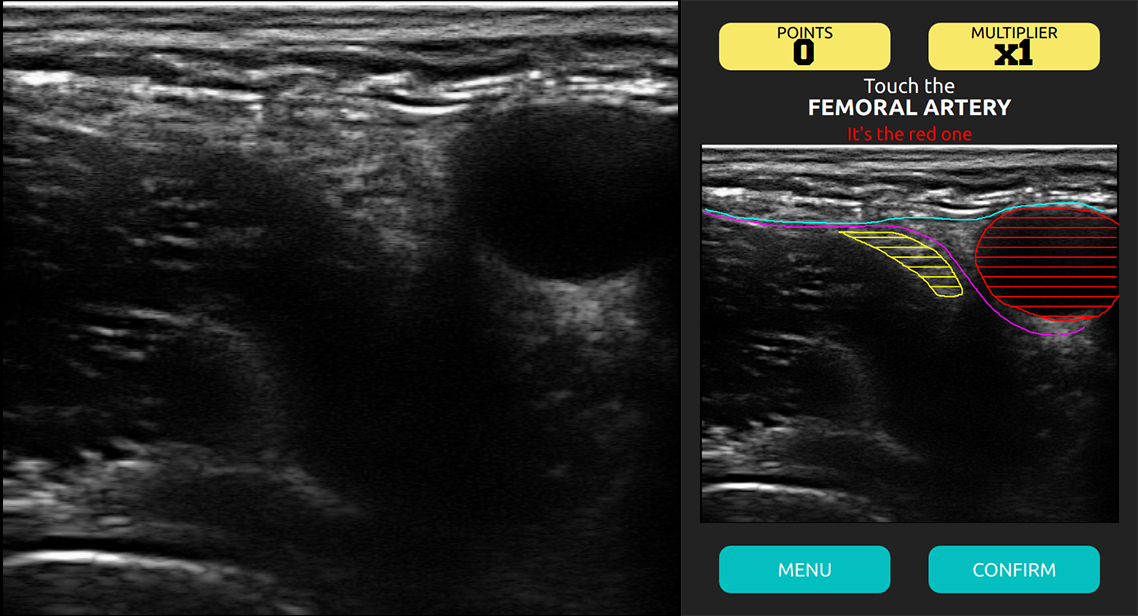

El juego tiene tres niveles de dificultad, por lo que los nuevos retos aparecen a medida que los "jugadores" se hacen mejores usándolo. En el primer nivel, se les da toda la ayuda que necesitan, pero en el más alto y más difícil, trabajan contra el tiempo. "Esto significa que siempre hay margen de mejora", dicen los estudiantes.

En el nivel más simple, la tarea es identificar la arteria (en rojo). En el más difícil, la tarea es la misma, pero sin ayuda, y en el menor tiempo posible. Fuente: Gemini.